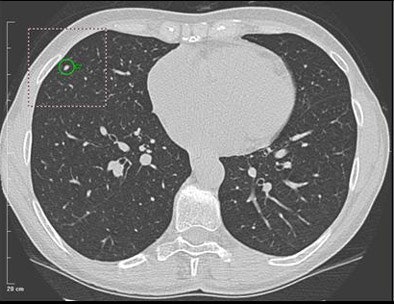

| A 5-mm nodule in right middle lobe, representing a true-positive CAD finding. All images courtesy of Dr. Heidi Roberts. |